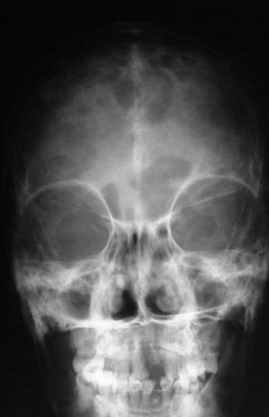

объем изменений совсем не возрастает по направлению к.периферии. В самых редких случаях в какой-то ничтожной

степени в процесс может быть вовлечен череп (часть нижней челюсти). Поражения ребер мы ни разу не наблюдали.